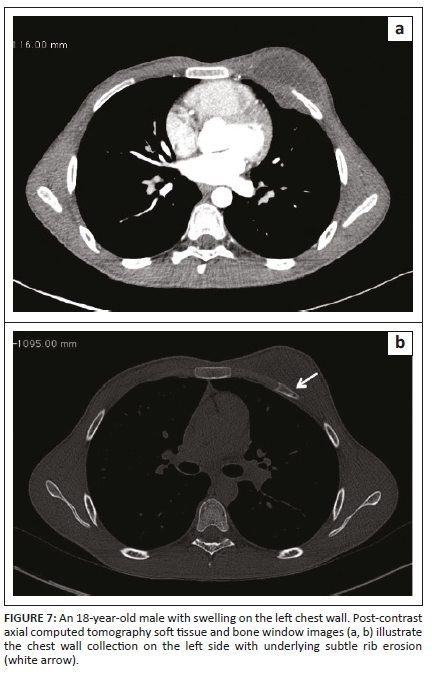

Tubercular involvement of ribs presents as either bony erosions with disruption of the cortical margin or frank destruction, with adjacent abscess formation.6,7 There may be focal expansion of the involved rib with or without periosteal reaction. Tuberculous abscesses of the chest wall can involve the sternum, costochondral junctions, rib shafts, costovertebral joints and the vertebrae.7 They are most frequently found at the margins of the sternum and along the rib shafts. A tuberculous retromammary abscess appears as a focal, smoothly marginated, inhomogeneous, hypodense lesion with a surrounding enhancing rim.13 A direct fistulous communication with the pleura or a destroyed rib fragment found in a tuberculous abscess can be helpful in differentiating it from other types of retromammary abscess.13,14 In the case of chest wall TB, the detection of underlying pleuro-parenchymal disease is often helpful in suggesting the diagnosis.3

Our patients demonstrated similar imaging findings, better documented on CT as lytic destruction or erosion of the sternum, clavicle, acromion, ribs and mandibular condyle. Soft tissue collections were detected around the bony involvement and this was also demonstrated on USG, where accessible. Ultrasonography showed the abscess as a hypo-echoic collection with posterior acoustic enhancement and varying degrees of internal heterogeneity. Some authors have also highlighted the use of USG as a cost-effective and useful modality to assess rib destruction/irregularity and associated soft tissue abscess in chest wall TB.6 In addition, USG provides real-time guidance for obtaining a tissue sample for pathological confirmation. The need for image guidance in accurately obtaining the tissue specimen from deep-seated collections/pathology, which is not appreciated clinically, is an important aspect of management, as the histopathological demonstration of caseous necrosis in the granulomas and microbiological identification in culture provides definite evidence of TB.2